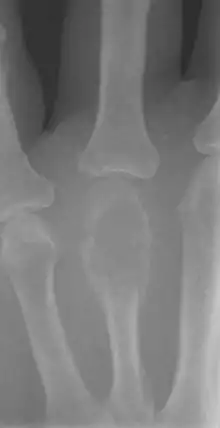

The most common bone tumor is a non-ossifying fibroma.[4] Average five-year survival in the United States after being diagnosed with bone and joint cancer is 67%.[5] The earliest known bone tumor was an osteosarcoma in a foot bone discovered in South Africa, between 1.6 and 1.8 million years ago.[6]